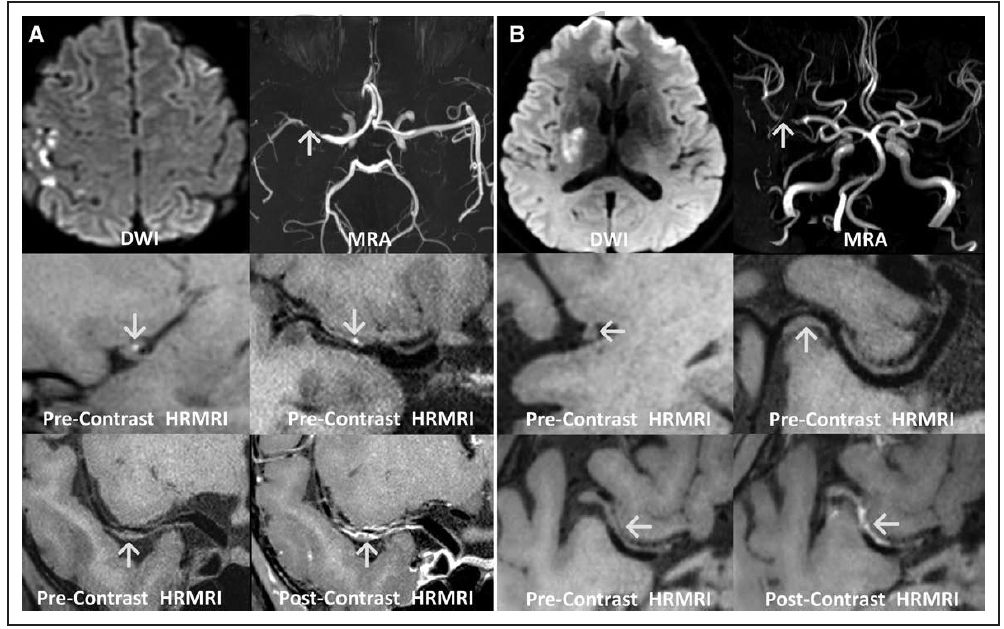

2015年1月至2017年5月期间,作者前瞻性地选择北京宣武医院神经内科的脑缺血性卒中患者;纳入研究标准,包括:症状出现的72小时内,经弥散加权成像(DWI)诊断为大脑中动脉(MCA)区新发急性缺血性脑卒中;经MRA、CTA或DSA确诊颈动脉颅内段或MCA狭窄。排除标准为:症状侧其它类型卒中或TIA发作史者;症状侧曾有颈动脉颅内段或MCA栓塞病史;超声检查发现,同侧颈动脉颅外段有>50%狭窄或不稳定斑块,此斑块具有以下特征:造成管腔狭窄>70%;呈纯低回声区或低回声区,或有小的高回声区;表面不规则,有溃疡;非动脉粥样硬化性血管病变,如血管炎、烟雾病等引起脑卒中;心脏栓塞性疾病,包含近3周内心肌梗死、房颤、二尖瓣狭窄或人工瓣膜、扩张型心肌病、病态窦综合征、急性细菌性心内膜炎和卵圆孔未闭等。最终纳入74例患者,平均年龄54.7±12.1岁,其中男性59例。所有患者均进行常规MRI、MRA和WB-HRMRI检查。根据弥散加权成像结果,将患者分为A-to-A栓塞性脑梗死组和非A-to-A栓塞性脑梗死组(图1);比较两组颅内动脉粥样硬化斑块的特点(表1)。

图1. A-to-A栓塞性脑梗死(图A)和非A-to-A栓塞性脑梗死组(图B)的MRI-DWI、MRA和HRMRI成像结果。